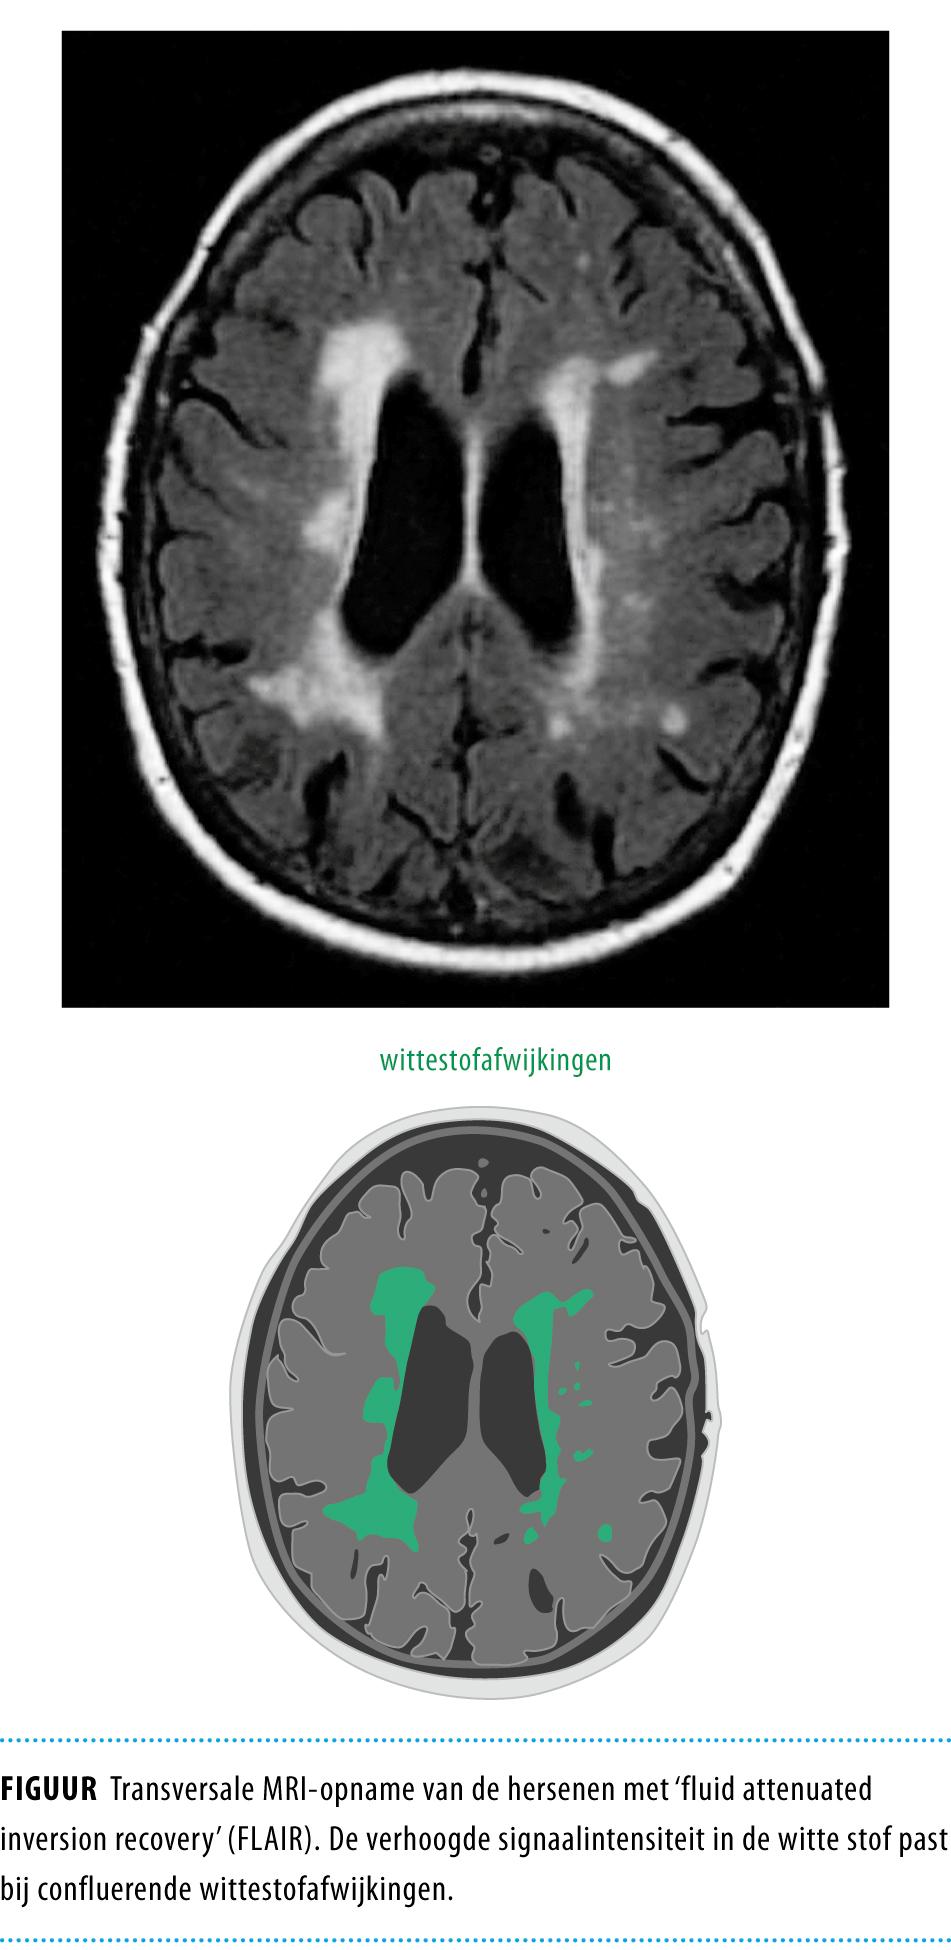

Bij patiënten met vasculaire risicofactoren komen cognitieve stoornissen vaker voor dan gedacht, zo is de afgelopen jaren gebleken. Vaak worden deze stoornissen niet herkend door hun behandelend arts.1,2 Dit komt zowel door het ontbreken van kennis van cognitieve stoornissen bij vasculaire aandoeningen in het algemeen, zoals hartfalen, diabetes en hypertensie, als door onbekendheid met de criteria voor cognitieve stoornissen. Patiënten met een cognitieve beperking van vasculaire oorsprong zijn soms bij de cardioloog onder controle in verband met hartfalen of bij de internist in verband met hypertensie en diabetes.1 De cognitieve problemen kunnen invaliderend zijn voor de patiënt en zijn of haar familie. Toch besteden de patiënt en de huisarts of specialist over het algemeen onvoldoende aandacht aan deze cognitieve functiestoornissen, omdat beiden de symptomen aan gewone veroudering toeschrijven.